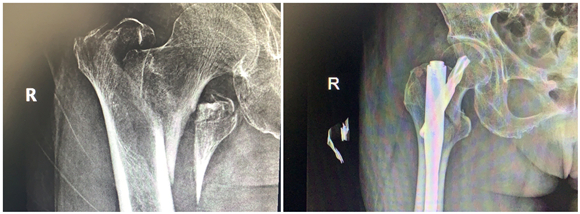

年前,蔡奶奶在家摔了一跤,右側(cè)股骨劇烈疼痛,不能走路,無法動(dòng)彈。檢查發(fā)現(xiàn)老人右側(cè)股骨粗隆間骨折,當(dāng)時(shí)老人拒絕治療,回家臥床后每況愈下。家人不忍心看著老人這么痛苦,了解到該院骨科擅長(zhǎng)老年性骨折治療,于是帶著老人來到該院鼓山路院區(qū)骨科就診。來院后,患者診斷為右股骨粗隆間粉碎骨折,并伴有右下肢深靜脈血栓、褥瘡、肺部感染等并發(fā)癥,情況非常危險(xiǎn),此類骨折又稱為“死亡骨折”。據(jù)了解,“死亡骨折”是指老年人的髖部骨折,常常是股骨粗隆間骨折和股骨頸骨折,其中骨折后臥床引起的并發(fā)癥會(huì)導(dǎo)致死亡,死亡率高達(dá)40%,又稱人生最后一次骨折。

此類手術(shù)風(fēng)險(xiǎn)大,醫(yī)生在告知患者家屬手術(shù)風(fēng)險(xiǎn)、術(shù)后康復(fù)、搶救方案等情況后,家屬打消了顧慮,決定盡快給老人家安排手術(shù),擺脫病痛折磨。同時(shí),麻醉科為老人制定了個(gè)性化的麻醉方案。王斌手術(shù)團(tuán)隊(duì)給患者制定了微創(chuàng)手術(shù)方案,通過三個(gè)小孔來進(jìn)行固定,避免了大的手術(shù)切口,整個(gè)手術(shù)過程僅僅耗時(shí)50分鐘,出血量50ml左右。

患者術(shù)后第二天就下地站立行走,X線顯示骨折對(duì)位好,復(fù)查下肢靜脈B超提示少許肌間靜脈血栓。在??漆t(yī)生的康復(fù)指導(dǎo)下,患者褥瘡、肺部感染也很快消失了。術(shù)后第7天,患者康復(fù)出院。